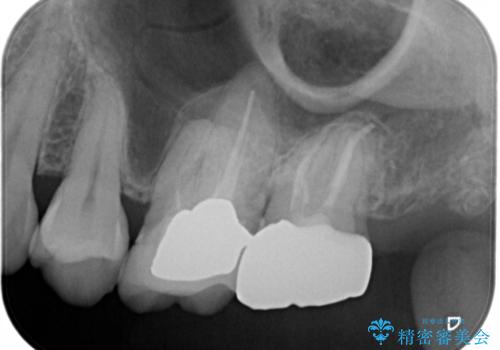

セラミックインレー 虫歯で欠けた歯の治療